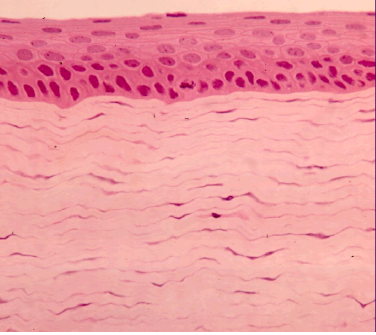

Question 8

Question

La presente fotografía corresponde a

Image:

25bc6272-893d-4ca6-b1f0-758a79ce9606 (image/png)

Answer

Córnea

Coroides

Retina